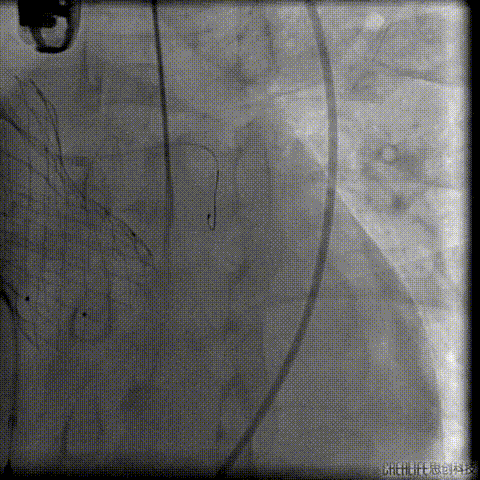

经瓣架网眼挂上指引管

反复确认指引管经瓣架网眼

指引管经瓣架网眼

经网眼置入导丝